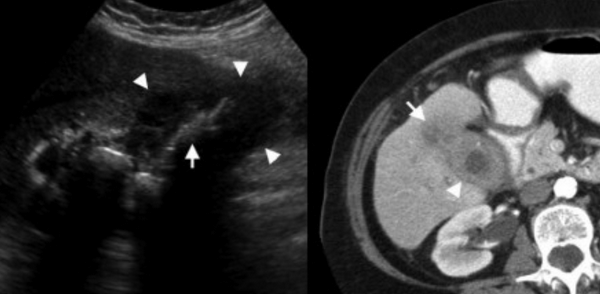

Слева — УЗИ — желчного пузыря у 59 летней женщины с острым холециститом. Субсерозный отек так, как гипоэхогенное утолщение между гиперэхогенными слоями (мышечным и слизистым). Справа — КТ брюшной полости с контрастным усилением. Также визуализируется субсерозный отек так, как наружный слой гиподенсный.

УЗИ и КТ желчного пузыря. Ксантогранулематозный холецистит. Слева на УЗИ визуализируется (помечено стрелками) утолщение стенки желчного пузыря с интрамуральным включением и с камнем в просвете органа. Справа на КТ выявляется утолщение стенки с гиподенсными включениями.

УЗИ (слева) и КТ (справа) желчного пузыря. На УЗИ ярко выраженное утолщение стенки желчного пузыря (указаны белыми стрелками). Множественные камни в просвете желчного пузыря (указано стрелкой). Компьютерная томография с контрастным усилением. На КТ визуализируются утолщение стенки с внутристеночными гиподенсными включениями. На КТ также выявлено, что процесс распространился на печень (указано стрелкой).